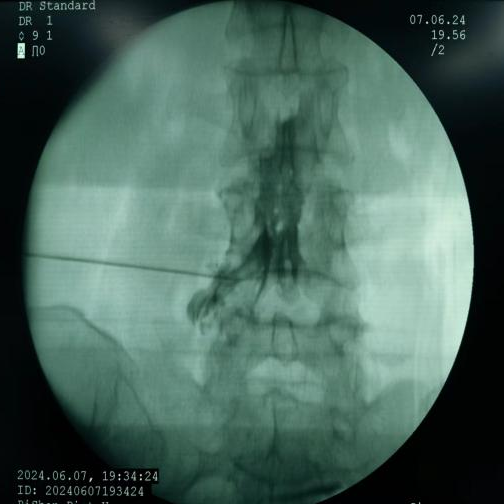

椎间盘射频消融术、胶原酶椎间盘化学消融术:两种都是治疗椎间盘突出症的微创介入技术。射频消融通过高频电流汽化部分髓核,胶原酶则是通过化学酶溶解髓核,均能降低椎间盘压力,从而解除神经压迫。

椎间盘射频消融术、胶原酶椎间盘化学消融术